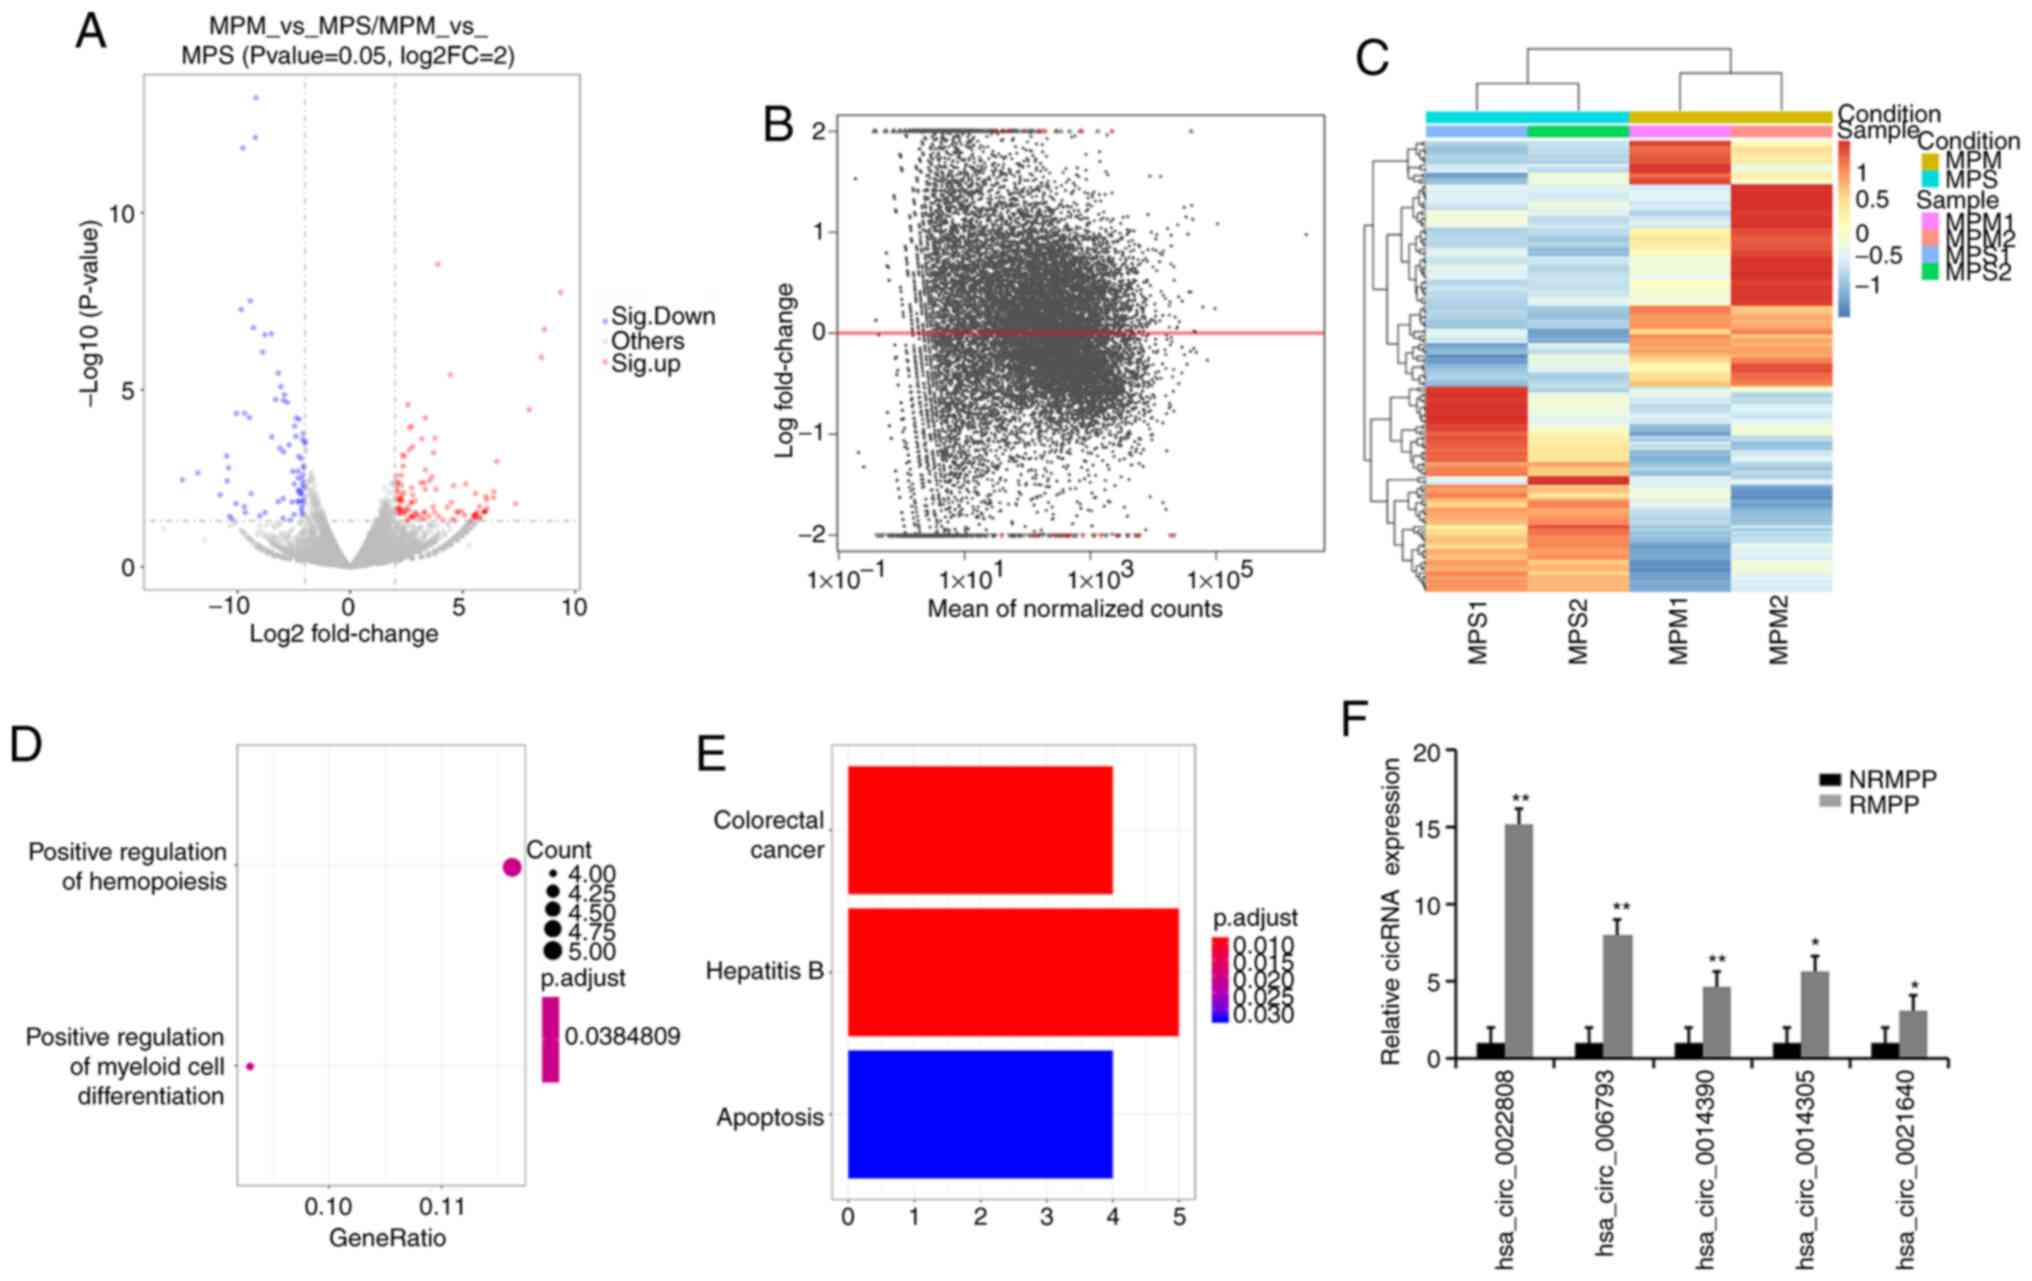

A total of 156 circRNAs (85 upregulated and 71 downregulated) were significantly differentially expressed (P<0.05) between the NRMPP and RMPP groups (Fig. 6A-C). A total of 24 circRNAs were identified as the most significantly differentially expressed circRNAs between the NRMPP and RMPP groups. In the GO analysis, GO terms were primarily enriched in ‘positive regulation of myeloid cell differentiation’ and ‘positive regulation of hemopoiesis’ (Fig. 6D). The screened circRNAs (Table VI) were primarily enriched in ‘colorectal cancer’, ‘hepatitis B’ and ‘apoptosis’ (Fig. 6E). The top five upregulated circRNAs were selected for further validation by performing RT-qPCR (Fig. 6F), indicating that these circRNAs may serve as potential biomarkers for RMPP.

In the present circRNA/mRNA analysis, circRNA function was found to be associated with the known function of the host linear transcripts. Based on the circRNA/miRNA/mRNA analysis conducted in the present study, several differentially expressed mRNAs were identified to be associated with the differentially expressed circRNAs. A total of 11 circRNAs were identified as the most significantly differentially expressed circRNAs between the HC and MPP groups. Among those, hsa_circ_0019868 [SH3 and PX domain-containing protein 2A (SH3PXD2A) gene] may be associated with MPP pathogenesis. SH3PXD2A is an adapter protein involved in the invasiveness of cancer cells that mediates the neurotoxic effect of the amyloid-β peptide (37). The higher expression in MPP groups may enhance the invasiveness of M. pneumoniae. A total of 24 circRNAs were identified as the most significantly differentially expressed circRNAs between the NRMPP and RMPP groups. Among their target genes, hsa_circ_0001890 [target of rapamycin complex 2 subunit MAPKAP1 (MAPKAP1) gene], hsa_circ_0026524 (eukaryotic translation initiation factor 4B gene), hsa_circ_0021640 [caprin-1 (CAPRIN1) gene], hsa_circ_0003781 [protein arginine N-methyltransferase 2 (PRMT2) gene], hsa_circ_0010131 [ephrin type-A receptor 2 (EPHA2) gene], hsa_circ_0025209 [NOP2 nucleolar protein (NOP2) gene] and hsa_circ_0023925 [phosphatidylinositol-binding clathrin assembly protein (PICALM) gene] may be associated with the pathogenesis of RMPP. The identified genes display the following characteristics: MAPKAP1 is involved in ciliogenesis, regulates cell proliferation and survival (38), and may serve as a novel anti-infection and antifibrogenesis genomic locus in chronic schistosomiasis japonica (39); NOP2 is involved in a ribosomal large subunit assembly and regulates cell proliferation (40); PRMT2 is involved in the regulation of proliferation and promotes apoptosis (41); EPHA2 regulates migration, integrin-mediated adhesion, proliferation and differentiation of cells (42); CAPRIN1 may regulate cell proliferation and migration in multiple cell types (43); and PICALM serves an important role in several processes, such as internalization of cell receptors, synaptic transmission and removal of apoptotic cells (44). Therefore, these genes might be involved in the pathogenesis of RMPP, but further investigations are required. In addition, the selected circRNAs (hsa_circ_0022808, hsa_circ_0006793, hsa_circ_0014390, hsa_circ_0014305 and hsa_circ_00216400) may represent valuable markers for the diagnosis of patients with early-stage RMPP and NRMPP. However, there were limited samples used in the present study; therefore, future studies should use larger sample sizes.